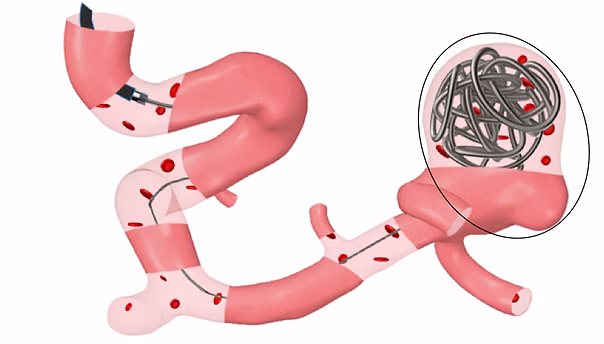

Monfared, M., Hollingsworth, L., Gamage, P.T., Taebi, A. (2025).

Assessing Hemodynamic Changes in Cerebral Aneurysms Post Coil Embolization: A Preliminary Investigation.

ASME Journal of Engineering and Science in Medical Diagnostics and Therapy, 8(3): 031014.​

flowCare Project

Taebi, A., Janibek, N., Goldman, R., Pillai, R., Vu, C., Roncali, E. (2022).

On the impact of injection distance to bifurcations on yttrium-90 distribution in liver cancer radioembolization.

Journal of Vascular and Interventional Radiology, 33(6): 668-677e1.

featured CME JVIR article of the month for June 2022

Taebi, A., Vu, C.T., Roncali, E. (2021).

Multiscale computational fluid dynamics modeling for personalized liver cancer radioembolization dosimetry.

ASME Journal of Biomechanical Engineering, 143(1): 011002.

honorable mention for the 2022 Skalak Award, among top 3 papers published by JBME in 2021 & 2022: 10.1115/1.4065051

Taebi, A., Pillai, R., Roudsari, B., Vu, C., Roncali, E. (2020).

Computational modeling of the liver arterial blood flow for microsphere therapy: Effect of boundary conditions.

Bioengineering, 7(3): 64.

Roncali, E.,Taebi, A., Roudsari, B.S., Vu, C.T. (2020).

Personalized dosimetry for liver cancer radioembolization based on computational fluid dynamics.

Annals of Biomedical Engineering, 48(5): 1499-1510.